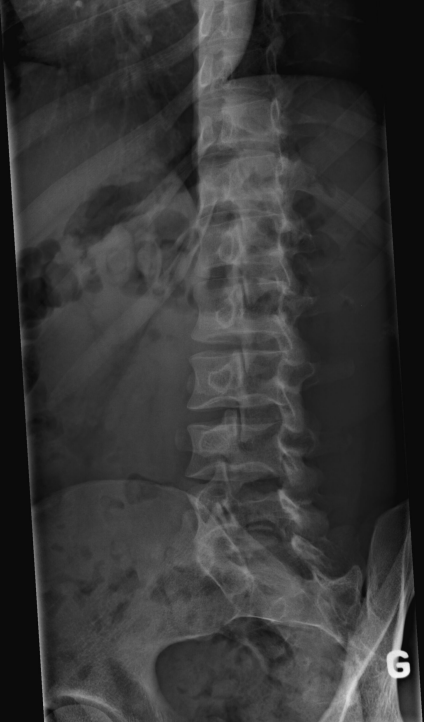

Concernant le rachis lombaire

Les processus articulaires supérieur et inférieur sont vus de profil.

Les articulations zygapophysaires du côté appuyé (D) sont démontrées.

Les pédicules du côté appuyé (D) sont projetés dans le tiers antérieur des corps vertébraux.

Les articulations zygapophysaires du côté appuyé (D) sont projetées au centre des corps vertébraux